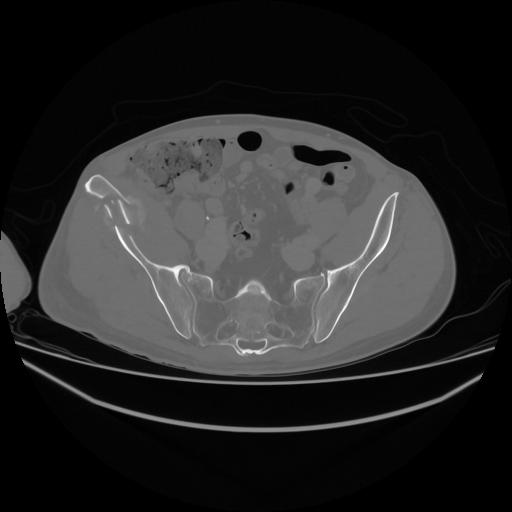

5 CUERPO,CE,Vol,1.0,CUERPO,,